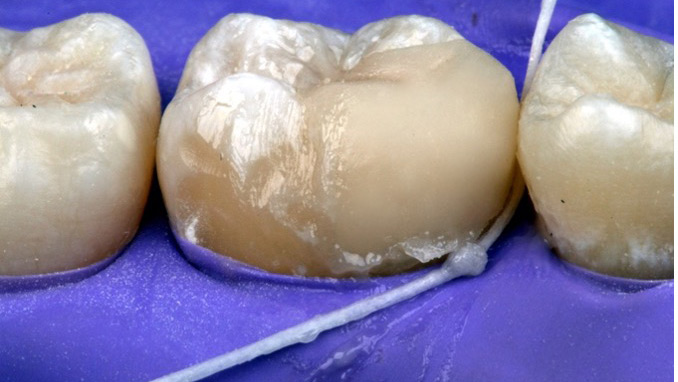

A New Tool for Cleaning Excess Resin Cement

Lawson-fig1-thumbnail alternate text for this image

Cleaning excess cement after cementation of a crown is a tedious but important clinical procedure. Failure to remove excess cement can lead to plaque accumulation, gingival inflammation and possibly even bone loss.1 Removal of cement is even more difficult when using resin cement. A recent Practice Based Research Network study reported that almost 40 percent … Read more